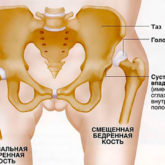

Berendezés kezelésére egy közös bizonyított hatású a különböző betegségek kezelésére az ízületek. kiküszöbölve fájdalom és gyulladás, elősegítik a szövetek regenerálódását és a méreg megszüntetése képződött ödéma. De, mint egy független terápiás szer az ilyen eszközöket nem használják, és része a komplex terápia formájában, amely az eszköz fizikoterápiás. Mivel az ilyen eszközök eltérnek a módszert az expozíció és ellenjavallatok. Felhasználás előtt győződjön meg róla, hogy konzultáljon orvosával.